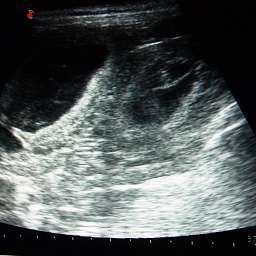

2 Fruchthüllen sind zu sehen

1 Fruchthülle ist zu sehen

Die Fotos sind übrigens durch Anklicken vergrößerbar. Ein Filmchen vom Ultraschall folgt noch. Im Moment fehlt nur die passende Technik zum Hochladen.